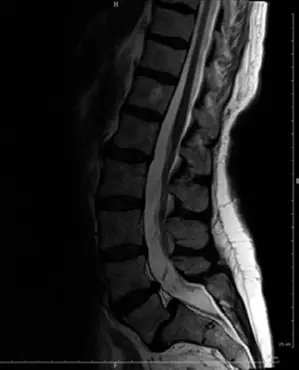

التصوير بالرنين المغناطيسي (MRI):

- يُعد التصوير بالرنين المغناطيسي الأداة الأكثر قيمة لتقييم الأنسجة الرخوة.

- يُظهر بوضوح الحبل الشوكي، جذور الأعصاب، الأقراص الفقرية، والأربطة.

- يكشف عن أي ضغط على الأعصاب بسبب الانزلاق، تضيق القناة الشوكية (Spinal Stenosis)، أو انزلاق غضروفي مصاحب.

- يُظهر أيضًا أي تورم أو التهاب حول البارس في حالات كسور الإجهاد النشطة.